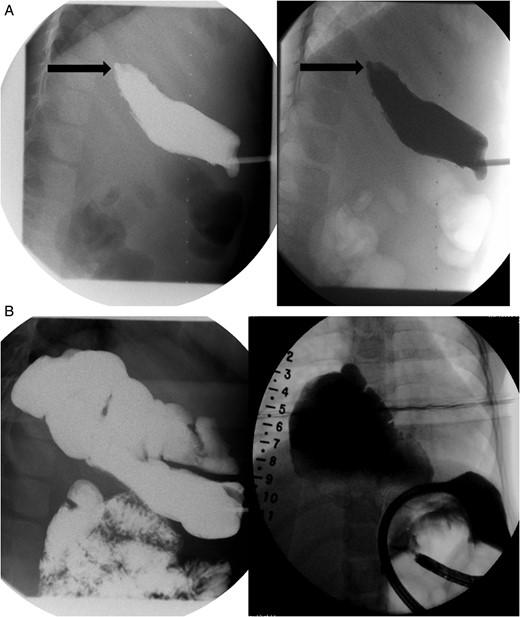

Daily tightening of her traction sutures was performed until the distal esophageal segment reached the chest wall (Fig. 2). The cervical esophagostomy was also sequentially lengthened and eventually internalized. Three traction suture revisions and two proximal esophageal lengthening operations were performed before esophageal continuity was re-established (46 days). Two subsequent anastomotic leaks occurred; 1 anastomotic leak was repaired surgically, whereas one subsequent leak was managed nonoperatively with a chest tube. Five dilations and, one, 13-day retrievable stent placement were needed for anastomotic narrowing. A comparative postoperative esophagram and intraoperative esophagram illustrated neither a stricture nor an anastomotic leak (Fig. 3). Total hospitalization was 112 days.

An intraoperative esophagram following a routine esophagogastroduodenoscopy (EGD) is pictured on the right, as compared with her postoperative esophagram on the left. The EGD was performed on this patient following her anastomosis (Foker Stage II); the native esophagus was now in continuity. Contrast was injected above the level of the anastomosis, which demonstrated neither leak nor stricture.